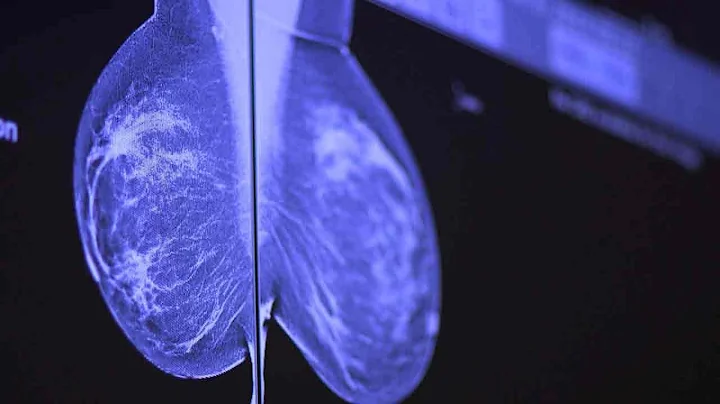

29: Mammograms Explained: How Early Detection Saves Lives